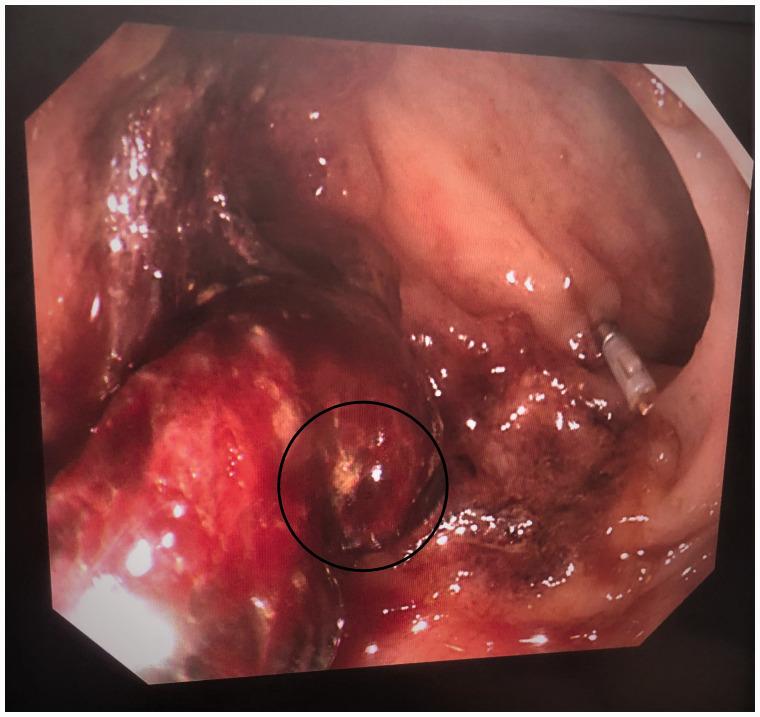

A 63-year-old woman was admitted to our hospital with herpes zoster viral infection and intermittent disorder of consciousness. On day 13 of hospitalization for glucocorticoid treatment, the patient experienced seven episodes of hematochezia. She had a 2-year history of systemic lupus erythematosus and had undergone splenectomy at 40 years of age. Computed tomography and electronic endoscopy revealed bleeding and contrast agent leakage into the splenic flexure of the colon. The patient underwent an emergency exploratory laparotomy and left hemicolectomy for suspected active hemorrhaging into the digestive tract. Pathological examination revealed that the bleeding had been caused by a fungal infection. No further hemorrhaging occurred after the surgery, suggesting that intestinal fungal infection might be a potential differential diagnosis for gastrointestinal bleeding in compromised hosts.

一名63岁女性因带状疱疹病毒感染和意识间歇性障碍入住我院。在住院第13天接受糖皮质激素治疗时,患者出现了7次便血。她有2年的系统性红斑狼疮病史,40岁时接受了脾切除术。计算机断层扫描和电子内窥镜检查显示结肠脾曲有出血和造影剂渗漏。患者因怀疑消化道有活动性出血接受了急诊剖腹探查术和左半结肠切除术。病理检查显示出血是由真菌感染引起的。术后未再发生出血,提示肠道真菌感染可能是免疫功能低下宿主胃肠道出血的一个潜在鉴别诊断。